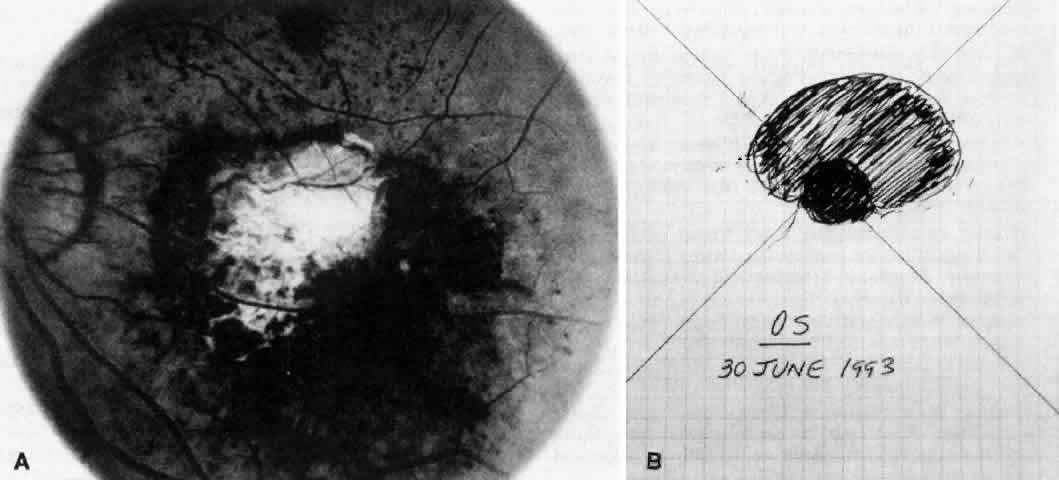

The placement of the retinotomy takes into account (1) the exact location of the membrane under the fovea; (2) the presence of presumed adhesions between the neurosensory retina and underlying tissue (previous photocoagulation scars and/or evidence of pigment migration into neurosensory retina or retinochoroidal vascular anastomoses); (3) the dimensions of the subretinal instruments (specifically the length of the angled instrument tips that determines how far away from the fovea the retinotomy can be made and still allow the tips to reach the membrane); and (4) the topographic anatomy of the neurosensory retina and nerve fiber layer. (A retinotomy made temporally in the macula disrupts less nerve fibers than does a retinotomy made nasally or superiorly that risks the creation of an arcuate visual field defect or reduced central acuity secondary to the interruption of the papillomacular bundle.) In most cases, these factors dictate a straight temporal or slightly superotemporal location for the retinotomy. However, the surgeon may choose to create a retinotomy superonasal to the fovea. With newer 33- and 36-gauge instruments, the retinotomies are small enough that no significant damage to the papillomacular bundle occurs. This approach may allow the surgeon to use his or her dominant hand for subretinal manipulation.

Besides being in the most advantageous location, the retinotomy should be as small as possible. Initially, we lightly diathermized the surface of the retina and then used the myringotomy blade to tease open a small hole through which an angled infusion needle was introduced.15 At the suggestion of Lambert and co-workers at Emory University, we stopped using diathermy. We now use a 120° angled, sharply pointed 36-gauge subretinal pick to pierce undiathermized neurosensory retina (Fig. 2). Occasional slight retinal hemorrhage can be controlled by transiently increasing the intraocular pressure. After the tiny hole has been made, the surgeon introduces the angled 33-gauge infusion needle beneath the retina and the assistant gently infuses balanced salt solution to elevate the neurosensory retina. This is accomplished by pushing on the plunger of a syringe that is connected to the hub of the needle by a short piece of tubing. As the fluid enters the subretinal space, attention is directed to edges of laser scars and/or adhesions to the underlying membrane (Fig. 3). Excessive infusion pressure can easily tear the retina. If areas of retina remain adherent, the infusion is stopped and the tip of an angled subretinal pick is carefully passed over the anterior surface of the membrane surface to break any residual adhesions. In a similar manner, the tip of the angled subretinal pick can be used to gently separate the thinned retina from an underlying photocoagulation scar. Occasionally, horizontal subretinal scissors are necessary to cut firm adhesions. These scissors have a similar 130° bend and blades approximately 3 mm in length to allow manipulation through an eccentric retinotomy. Trauma to foveal photoreceptors from either the pick or scissors is carefully avoided. If the retina is not mobilized over the entire photocoagulation scar, separation is achieved at least far enough into the scar to allow manipulation and extraction of the membrane without tearing the adjacent retina. The sharp tip of the angled subretinal pick is used to elevate the edge of the neovascular complex from the underlying RPE (Fig. 4). Care is taken to swing the pick in a pivoting or rotating manner to stretch or enlarge the retinotomy as little as possible. This requires close attention not only to the primary site of action at the membrane but also to the instrument shaft at the retinotomy site. In the appropriate cases, the complex dislodges easily from the underlying subfoveal RPE but remains attached to the edge of a laser scar (in recurrent cases) or to the stalk of choroidal vascular ingrowth.

We use positive action horizontal forceps that are angled 130° and have tips 3.2 mm in length.15 The tips are introduced (closed) through the retinotomy, which has usually enlarged slightly during the subretinal manipulation. The objective is to place the opened blades around the stalk or the adhesion, with the membrane in front of the blades. Gentle traction with the blades held closed breaks the connection (Fig. 5). This step is performed slowly and carefully. If traction on the retina is seen, the membrane is released and further separation of the complex from neurosensory retina is accomplished. If excessive tugging and displacement of surrounding RPE is seen, then consideration is given to using the subretinal scissors to cut the stalk rather than breaking it with the forceps. In virtually every case, the membrane (and often the adjacent laser scar) can be removed in one piece. As pathologic examination has confirmed, the abundance of cohesive basement membrane material matrix surrounding occasional capillaries, creates a complex of significant tensile strength.14

When the vascular connection from the choroid is about to be severed, the intraocular pressure is raised to approximately 80 mm/Hg. Despite this precaution, minimal hemorrhage is often countered when the membrane is removed. In one early case, while attention was directed to removing the neovascular complex through the sclerotomy, a massive hemorrhage occurred beneath the retina. In two additional cases, enough blood accumulated in the subretinal space to require removal with subretinal forceps. We now maintain the intraocular pressure elevated for at least 1 minute and watch closely for any evidence of rebleeding while the pressure is slowly lowered. If more bleeding occurs, the intraocular pressure is raised again. After the implementation of these measures, significant subretinal hemorrhage has not occurred in the last 60 cases.

Once hemostasis is achieved, the membrane is extracted through the sclerotomy for pathologic examination or it is cut and aspirated with the vitrectomy probe. Occasionally, large membranes cannot be removed through a standard size sclerotomy. We prefer dividing the membrane into smaller pieces with intraocular scissors rather than enlarging the sclerotomy. Plugs are placed and scleral depression is performed 360° to verify that no peripheral retinal tears have occurred.

A complete air-fluid exchange is next performed. We use standard extrusion needles or silicone-tipped needles for the exchange, with the aspirating tip over the optic nerve. In early cases, once the retina was flat, endolaser burns were applied around the retinotomy. The resulting laser scars were eccentric from the fovea but did occasionally produce symptomatic scotomas. In the past 60 cases, we have used no laser and have found the retina to remain attached. Our use of intraocular tamponade has also undergone evolution. Initially, we used nonexpansile concentrations of sulfur hexafluoride or perfluoropropane and encouraged facedown positioning for 1 to 2 weeks. As improved instrumentation allowed smaller retinotomies, we have questioned the need for gas tamponade. We perform fluid-air exchange and leave the eye with a one-half to two-thirds fill of filtered air. In the most recent 15 cases, we have gently reinfused balanced salt solution over the optic nerve after the vitreous cavity has been dry for a few minutes. The eye is completely filled with fluid, and no special positioning is used. In each of these cases, the posterior hyaloid has been meticulously removed. In each case the retinotomy has sealed without gas tamponade. Additional cases will be required before this modification can be widely advised.